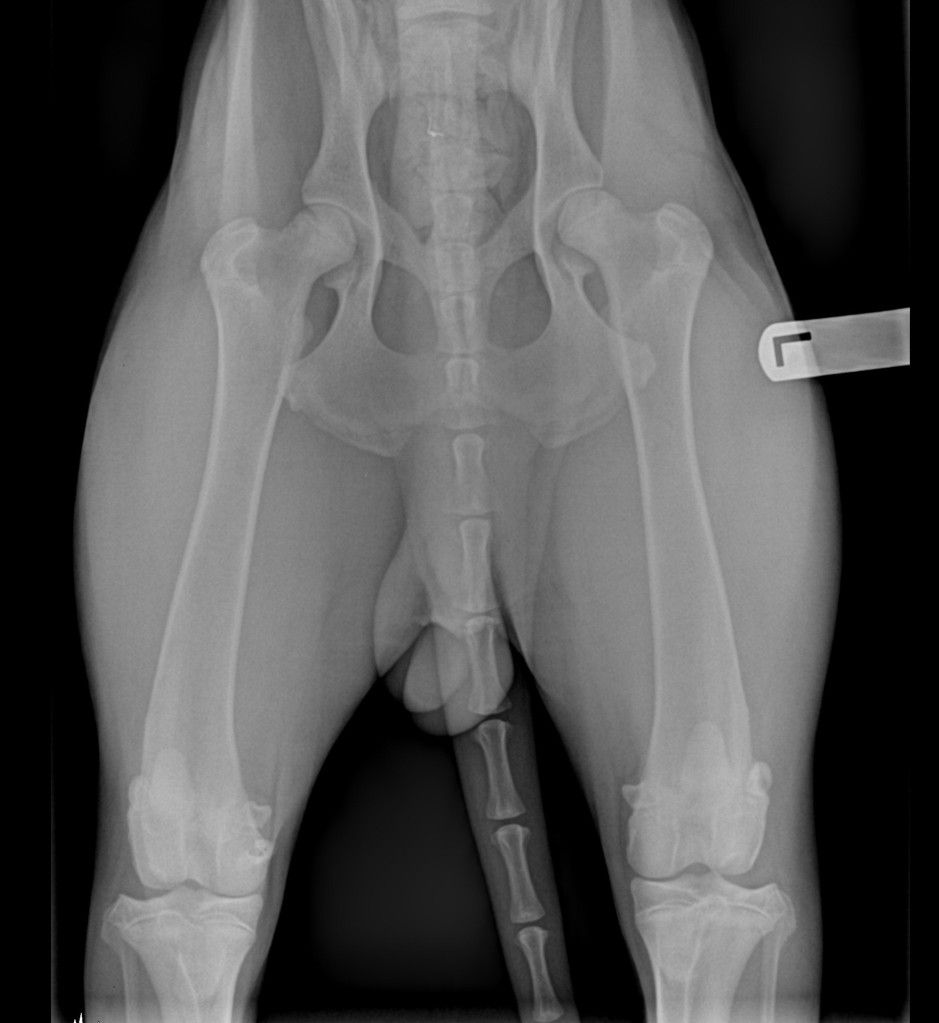

Your opinions please. 9 month old prelims. Thank you in advance.

Best guess OFA prelim good to excellent.

Looks good to me. Hopefully, AKC might consider them excellent...

Very nice excellent looking hips, good for you!